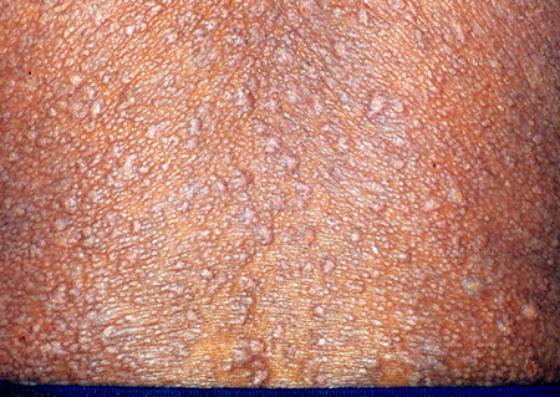

2. 典型皮损为淡红色及黄色丘疹,0.2~0.4cm,  表面光滑,密集成群似苔藓样。

3. 皮损好发于前臂伸侧、面部、手背及躯干,可泛发,但常限局,排列成斑片状,线状,环状。+